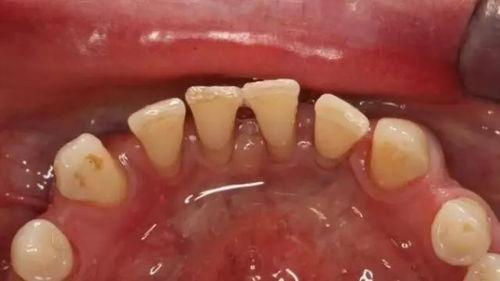

1. 清洁口腔:在进行牙周夹板固定之前,医生会先帮你彻底清洁口腔,确保口腔卫生。

6. 保持口腔卫生:牙周夹板固定期间,保持口腔卫生至关重要,否则容易引发口腔问题。

2. 清洁口腔:医生使用专业工具清洁患者口腔,确保口腔卫生。

7. 保持口腔卫生:医生提醒患者保持口腔卫生,避免口腔问题。

3. 保持口腔卫生:保持口腔卫生是牙周夹板固定期间的关键,否则容易引发口腔问题。